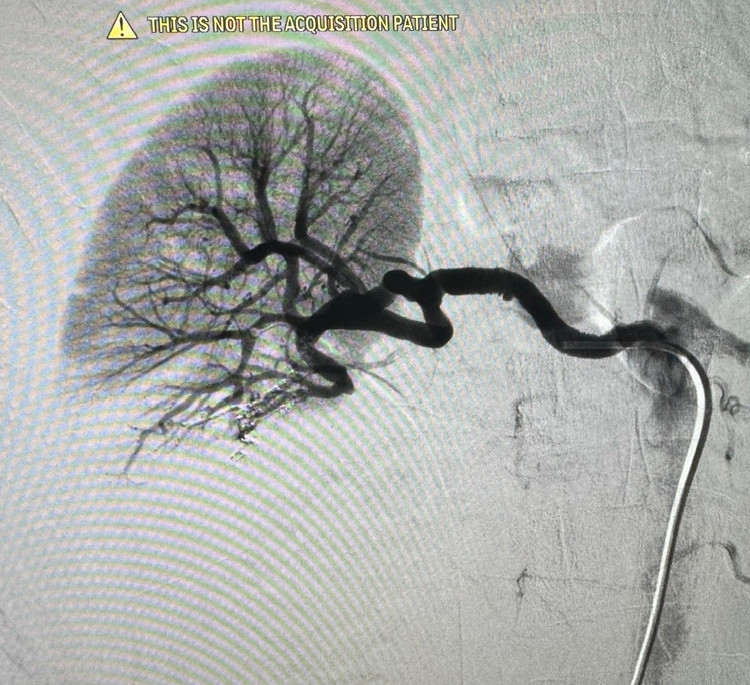

1h sáng ngày 14/7, tại phòng can thiệp – Bệnh viện Đa khoa Hùng Vương, các bác sĩ Khoa Chẩn đoán hình ảnh phối hợp Khoa Hồi sức cấp cứu đã nút mạch cầm máu thành công cho nam bệnh nhân 59 tuổi bị vỡ thận độ IV do tai nạn giao thông nghiêm trọng.

Hình ảnh CT ổ bụng ghi nhận: Vỡ thận phải độ IV; Chảy máu hoạt động; Tụ máu quanh thận. Đồng thời, bệnh nhân còn vỡ xương sọ và xương mặt.

Sau hội chẩn liên khoa bệnh nhân được tiên lượng rất nặng. Thay vì phải chuyển tuyến – tiềm ẩn nhiều rủi ro như sốc mất máu, ngừng tuần hoàn trên đường đi, bệnh nhân đã được xử trí kịp thời ngay tại tuyến cơ sở.

Trong tình huống nguy kịch, bệnh nhân đã được can thiệp nút mạch ngay trong đêm tại Bệnh viện Hùng Vương. Nhờ xử trí kịp thời, các bác sĩ đã kiểm soát chảy máu, bảo tồn tối đa nhu mô thận và giành lại sự sống cho người bệnh. Hiện bệnh nhân đang tiếp tục được theo dõi sát tại Khoa Hồi sức cấp cứu.